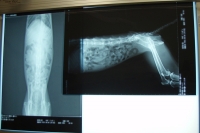

って事で、次はレントゲンとエコーを撮って貰った。

特に目立った問題は無いのだが、写真で腸内が黒く写っている=ガスが充満しているって事で、エコーでは正しい検査が出来なかった。